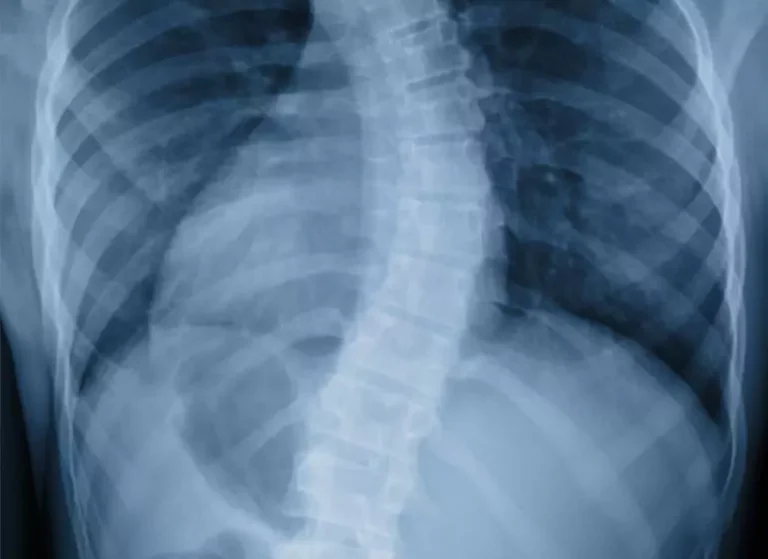

An x-ray image of a deformed spine.

Scoliosis

Thankfully, scoliosis is a manageable condition. However, there are cases where surgery becomes necessary. Noninvasive treatment options we offer includes chiropractic care, rehabilitative therapy and DRS System treatments.

Learn more about Scoliosis.